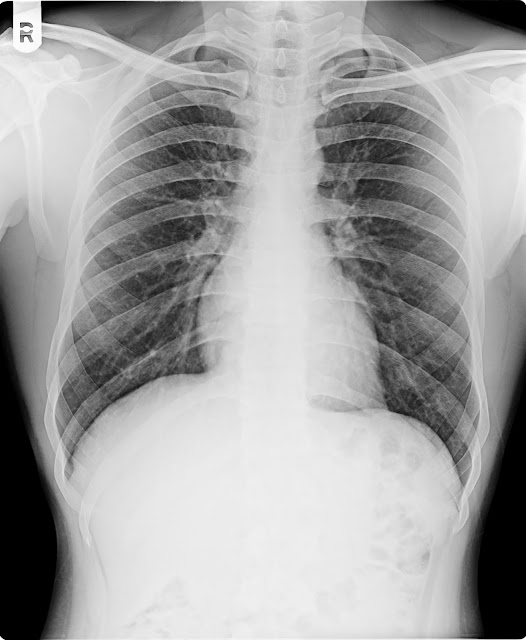

01\03\18 AKHILESH KUMAR M\23Y CXR-PA

H\O KHASHI LAST 8 DAYS

X-RAY CHEST

PA VIEW.

Both

lung fields appears normal.

No

evidence of koch’s lesion or consolidation seen.

apices, cardiophrenic, costophrenic angles and domes of the diaphragm are normal.

The

cardiac size is within normal limit.

Trachea

is central, no mediastinal shift is seen and the mediastinal outlines do not show any

abnormality.

Bony

thorax appear normal

IMPRESSION ;

NORMAL X RAY CHEST .